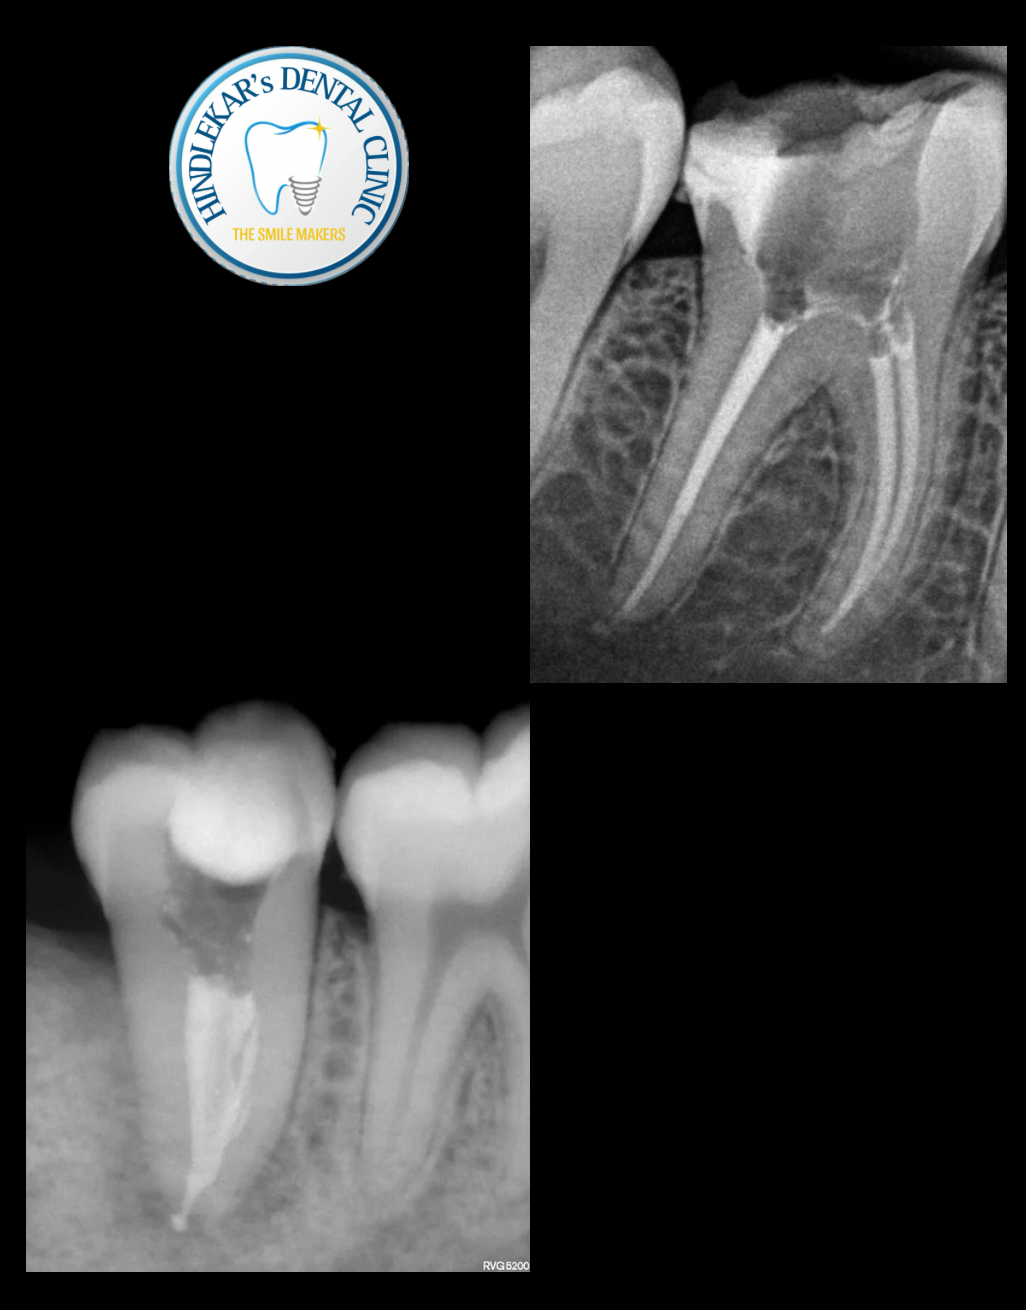

Best Root Canal Treatment in Balewadi

Handled by an experienced Endodontist (Root Canal Specialist) ✨ Single-visit RCT ✨ Re-root canal & difficult cases ✨ Advanced equipment & hygiene 📍 B-18, Espacio, Golden street Road, Balewadi ⭐⭐⭐⭐⭐ Patient-recommende Call for today’s appointment at Dr Ajit Hindlekar’s Dental Clinic..